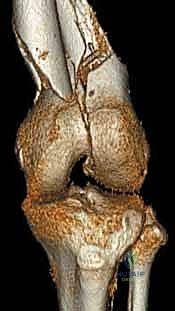

- الأشعة المقطعية (CT Scan): وهي ضرورية جداً في كسور عظم الفخذ البعيدة، خاصة إذا كان الكسر يمتد إلى داخل مفصل الركبة (Intra-articular fractures). تساعد الأشعة المقطعية الدكتور هطيف على بناء نموذج ثلاثي الأبعاد للكسر، مما يسهل التخطيط الجراحي وتحديد أماكن وضع المسامير بدقة.